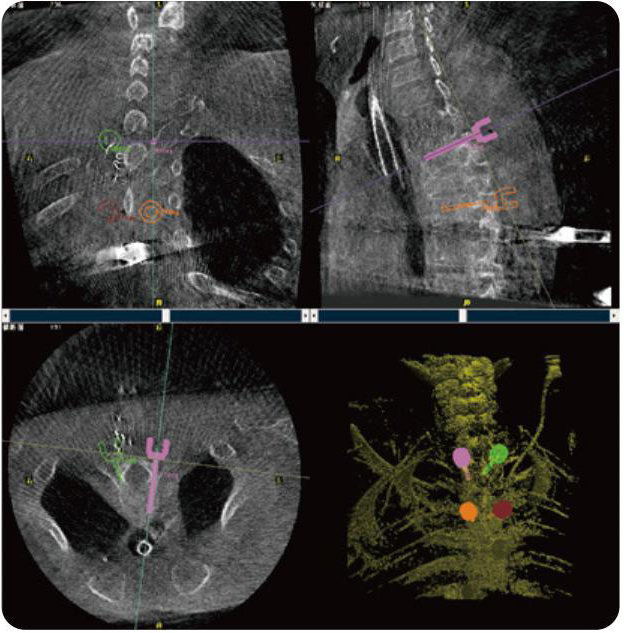

PL300B可應(yīng)用于多節(jié)段脊柱外科手術(shù),輔助醫(yī)生定位病灶部位,為脊柱外科手術(shù)(經(jīng)皮椎體成形術(shù)、椎弓根螺釘內(nèi)固定術(shù)等術(shù)式)提供術(shù)前手術(shù)流程規(guī)劃、入釘位置、角度可視化引導(dǎo),模擬仿真入釘輔助。

PL300B搭配普愛醫(yī)療自主研發(fā)生產(chǎn)的平板3D C形臂,借助一體化自適應(yīng)配準(zhǔn)( 軌跡配準(zhǔn))技術(shù),通過追蹤C(jī)形臂三維采集軌跡,自動(dòng)完成圖像坐標(biāo)建立和系統(tǒng)坐標(biāo)配準(zhǔn)。配準(zhǔn)精度更高,操作步驟少,系統(tǒng)運(yùn)作效率高。